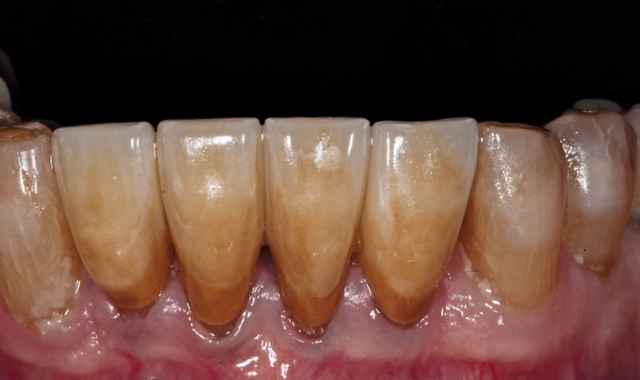

The patient then returned for final try-in and cementation of the definitive CAD/CAM restorations. Because the patient was directly involved in the diagnosis, evaluation, smile design, treatment planning and provisionalization evaluation-and because the final restorations were designed based on digital replicas of the approved

provisionals-there were no unanticipated results. In fact, no adjustments were needed to the contacts or occlusion, and the patient approved the esthetics. The splinted crowns were then cemented with resin reinforced glass ionomer cement (Figs. 21 and 22).